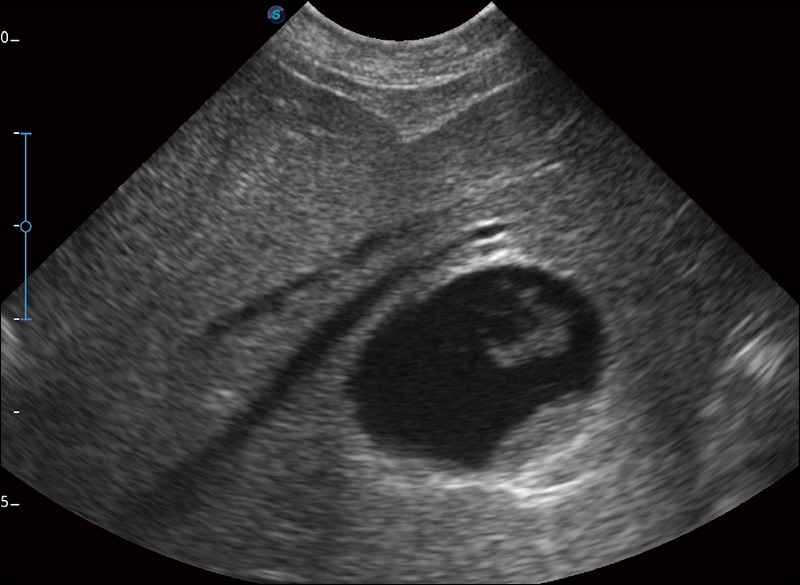

连续波多普勒成像CW

为心脏功能评估提供更多诊断信息